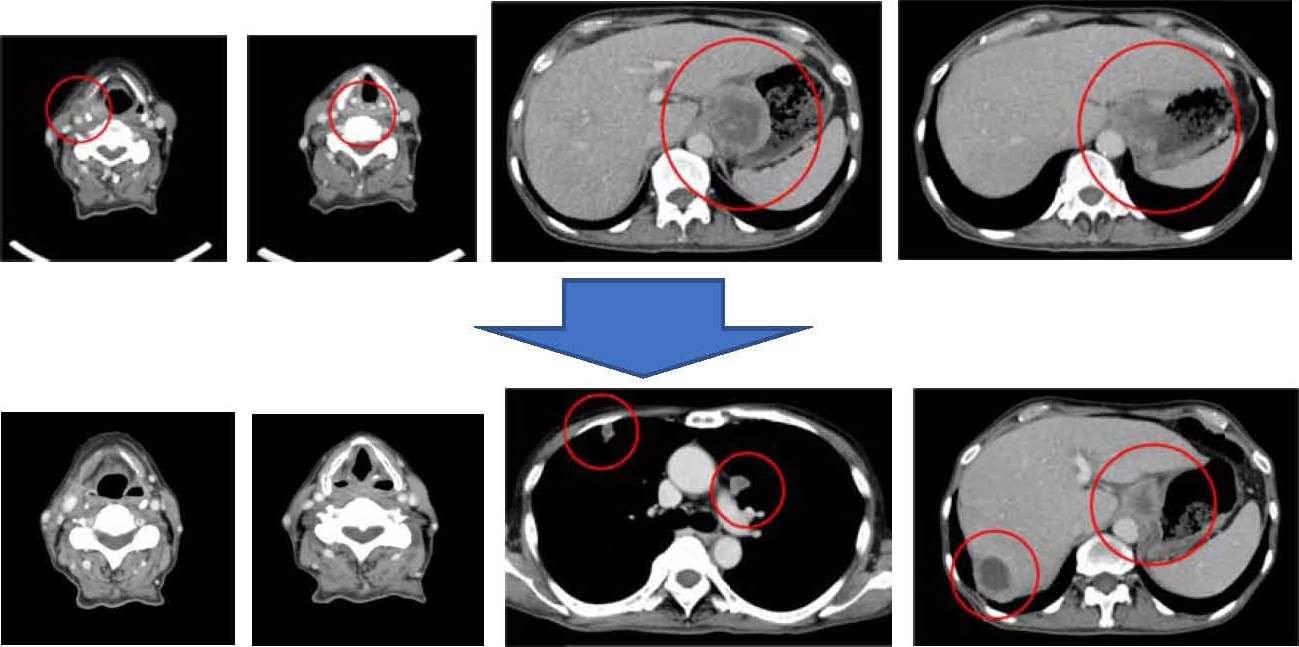

検査から抜けがちな頭頸部 意識的に検査し頭頸部がんを早期発見